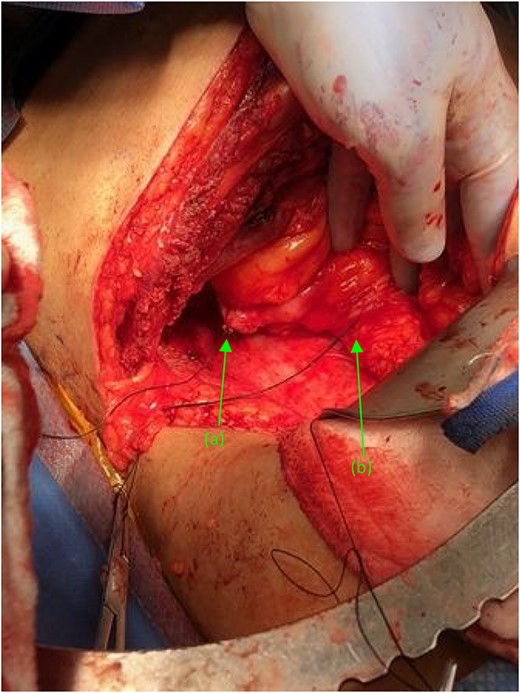

Given results of Mercaptiacetyltriglycerine (MAG3) renal scan, revealing a largely non-functioning right kidney (<10%), decision was made to proceed with nephrectomy and duodeno-ureteral fistula repair. A standard posterior nephrectomy approach was utilized, with the initial incision made at the level of the 12th rib, extending to the subcostal margin and cephalad through each layer of muscle from the external oblique to the internal oblique down to the transversalis fascia. The inflamed right ureter was noted just above the iliac artery and isolated using a vessel loop. Two fistulous connections were then identified. The first tract connected the renal pelvis to the second portion of the duodenum. The second fistula connected the proximal ureter to the third portion of the duodenum (Fig. 2). Both tracts were sharply dissected free, tagged with silk ties, and transected. The anterior dissection was extended medially until the right renal vein was identified. The renal hilum was then transected, as were the cephalad attachments (Fig. 3). The right adrenal gland was noted and spared. The kidney was then freed; the specimen was delivered and handed off the field.

Right kidney, status post nephrectomy, transected at the renal hilum. (a) First fistulous tract exiting the renal pelvis. (b) Second fistulous tract extending from its origin point off the proximal ureter and branching just distal to the ureters entry at the renal pelvis.